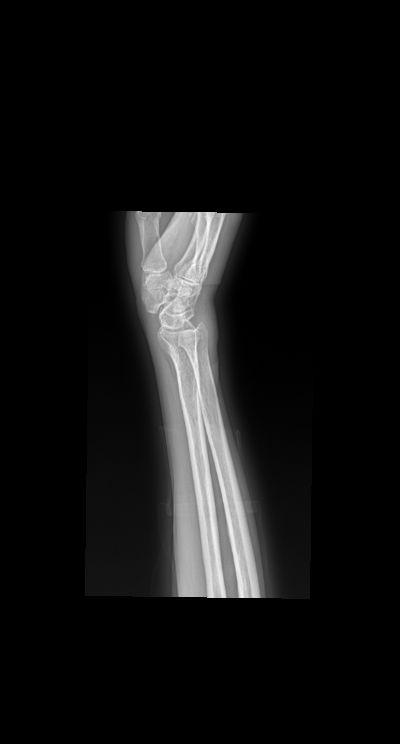

腕关节扭伤三天就诊 男 73y